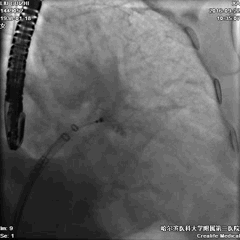

手术过程-PASS原则 封堵器释放及造影

Position:导引鞘及输送系统管缓慢回撤,远端展开顺利,位置适中。

手术过程—PASS原则,牵拉测试

Anchor:封堵器固定良好,TEE及DSA显示牵拉后无移位现象。

手术过程—PASS原则,封堵器压缩比

Size:24mm封堵器,压缩比16%-18%,径向支撑良好。

手术过程—PASS原则,残余分流

Seal:封堵器贴壁良好,各切面无残余分流。

手术过程—封堵器最终释放

PASS原则全部通过,封堵器释放,效果满意,手术结束。